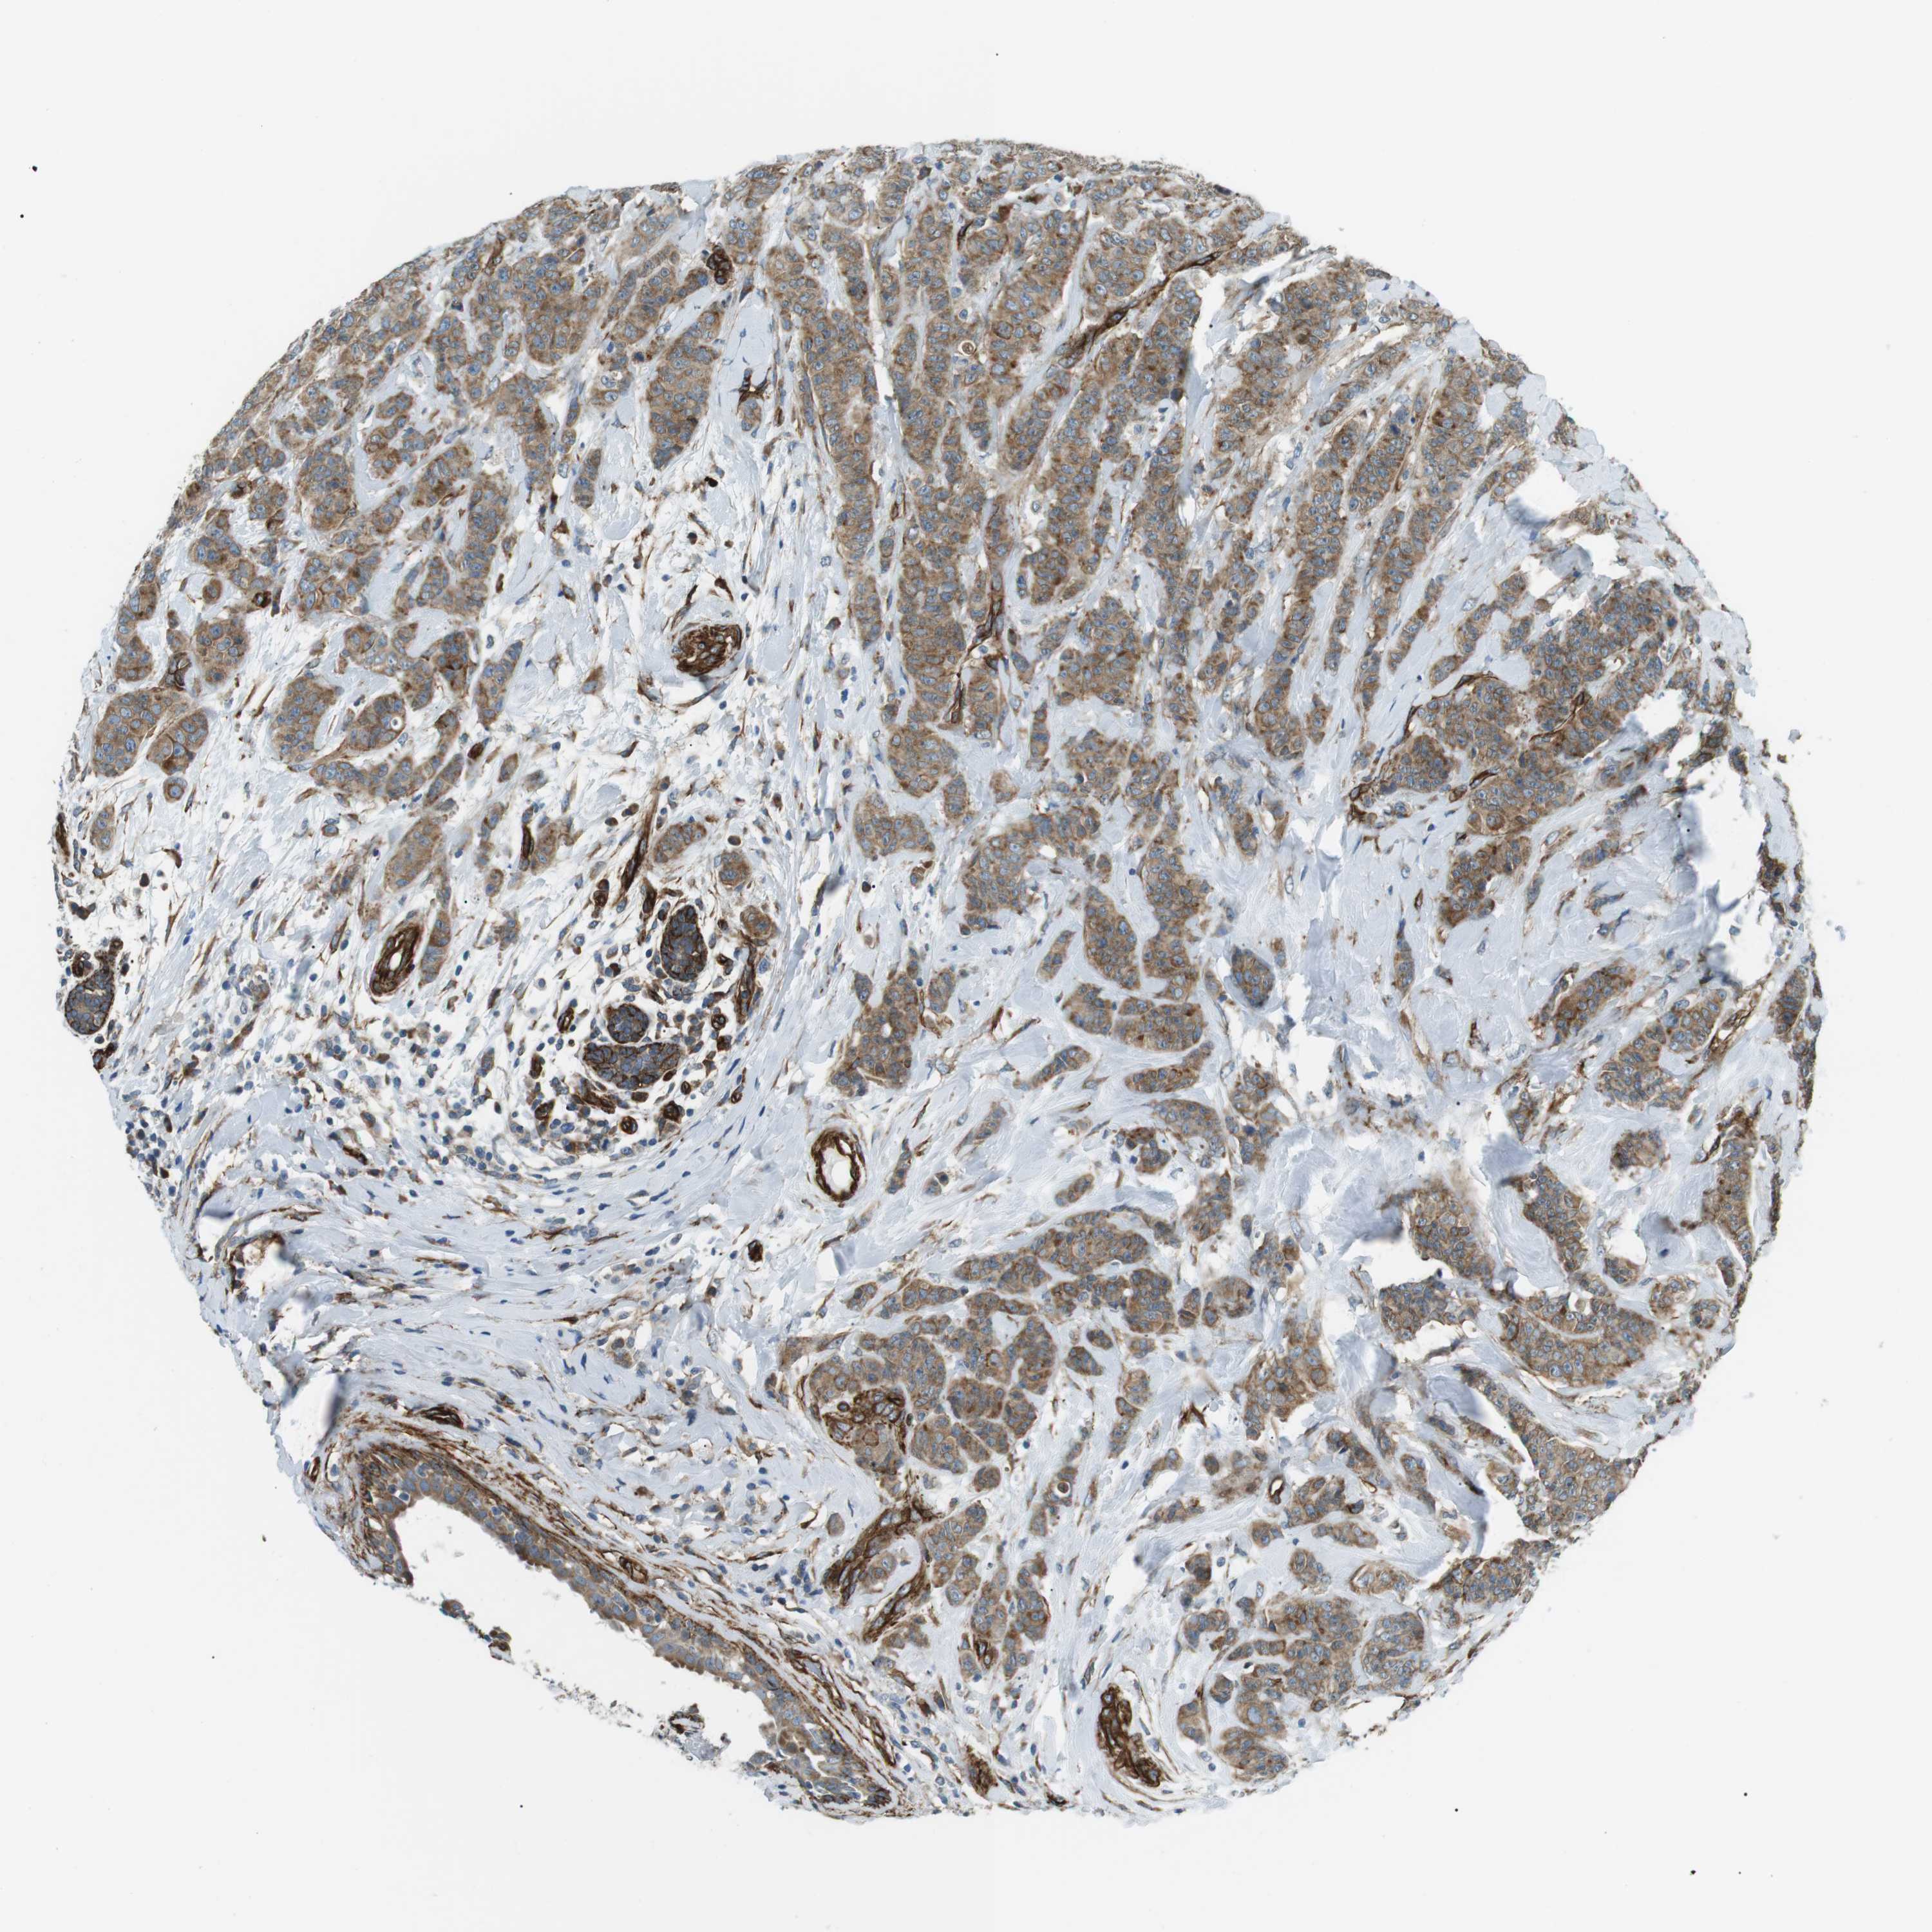

BRCA TCGA BRCA VALIDATION PROTEIN EXPRESSION

ANTIBODIES

AND

VALIDATION